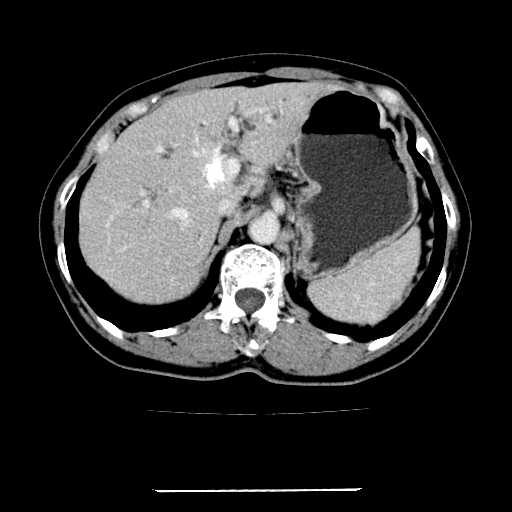

标题: CT22301:女,67岁,上腹部疼痛一周伴皮肤黄染,无发热。 [打印本页]

女,67岁,上腹部疼痛一周伴皮肤黄染,无发热。

左叶肝内胆管结石,并远端肝内胆管扩张。

肝内外胆管结石并肝内胆管扩张。

肝内外胆管扩张,左叶胆管内结石

建议薄层观察,除外肝门部胆管细胞癌

考虑肝胆管癌;胰头占位?【形态失常,体积增大】

1、肝门高密度影下层面和胰头层面可见轻度胆管扩张,而静脉和延迟期均未见扫描完胰头,不能完全排除胰头占位。2、肝门部高密度影,考虑钙化或结石。

考虑肝门胆管癌伴门脉左支受侵包埋,建议mrcp进一步检查。